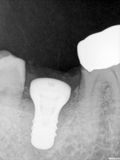

fredlibc | all galleries >> Galleries >> WYu - 47 implant > R6.jpg

R6.jpg